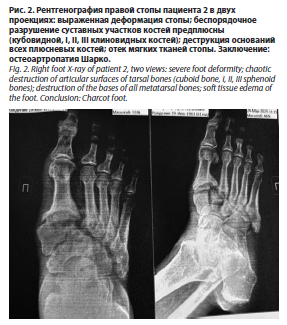

На момент поступления локальный статус (нижние конечности) пациентов имел следующие характеристики. Пациент 1: нижние конечности симметричны. Нарушены все виды чувствительности (вибрационная – 0, тактильная, болевая, температурная – снижены). Кожные покровы теплые на ощупь. Пульсация на бедренных и подколенных артериях сохранена с обеих сторон, на берцовых артериях и АТС – отсутствует. В области культи I пальца правой стопы – трофическая язва (некроз краевых лоскутов). На тыле левой стопы – трофическая язва (некроз тыла стопы размером 6,5×10 см с некрозом сухожилия разгибателя I пальца и вовлечением плюснефалангового сустава). Гиперкератоз на подошвах. Ногтевые пластины деформированы. Пациент 2 (рентгенография правой стопы – рис. 2): нижние конечности симметричные. Нарушены все виды чувствительности (вибрационная – 0, тактильная, болевая, температурная – снижены). Ампутационная культя V пальца левой стопы. Правая стопа умеренно отечна, свод уплощен, деформация костей плюсны, пролабирование кубовидной кости с формированием язвенного дефекта на подошвенной поверхности диаметром до 1 см, края раны плотные, гиперкератоз, скудное серозное отделяемое из раны. Пульсация на бедренных артериях сохранена, на подколенных артериях справа и слева – ослаблена, ниже – не определяется.

На момент поступления локальный статус (нижние конечности) пациентов имел следующие характеристики. Пациент 1: нижние конечности симметричны. Нарушены все виды чувствительности (вибрационная – 0, тактильная, болевая, температурная – снижены). Кожные покровы теплые на ощупь. Пульсация на бедренных и подколенных артериях сохранена с обеих сторон, на берцовых артериях и АТС – отсутствует. В области культи I пальца правой стопы – трофическая язва (некроз краевых лоскутов). На тыле левой стопы – трофическая язва (некроз тыла стопы размером 6,5×10 см с некрозом сухожилия разгибателя I пальца и вовлечением плюснефалангового сустава). Гиперкератоз на подошвах. Ногтевые пластины деформированы. Пациент 2 (рентгенография правой стопы – рис. 2): нижние конечности симметричные. Нарушены все виды чувствительности (вибрационная – 0, тактильная, болевая, температурная – снижены). Ампутационная культя V пальца левой стопы. Правая стопа умеренно отечна, свод уплощен, деформация костей плюсны, пролабирование кубовидной кости с формированием язвенного дефекта на подошвенной поверхности диаметром до 1 см, края раны плотные, гиперкератоз, скудное серозное отделяемое из раны. Пульсация на бедренных артериях сохранена, на подколенных артериях справа и слева – ослаблена, ниже – не определяется. У пациентов с СД2, в отличие от здоровых доноров, наблюдалась повышенная способность нейтрофилов к образованию НВЛ при стимуляции как пробиотиком, так и тромбином (рис. 3–5). При этом нейтрофилы пациента с НОА (стопа Шарко) демонстрировали более выраженное формирование нитевидных НВЛ по сравнению с нейтрофилами пациента с СДС (рис. 4, 5).